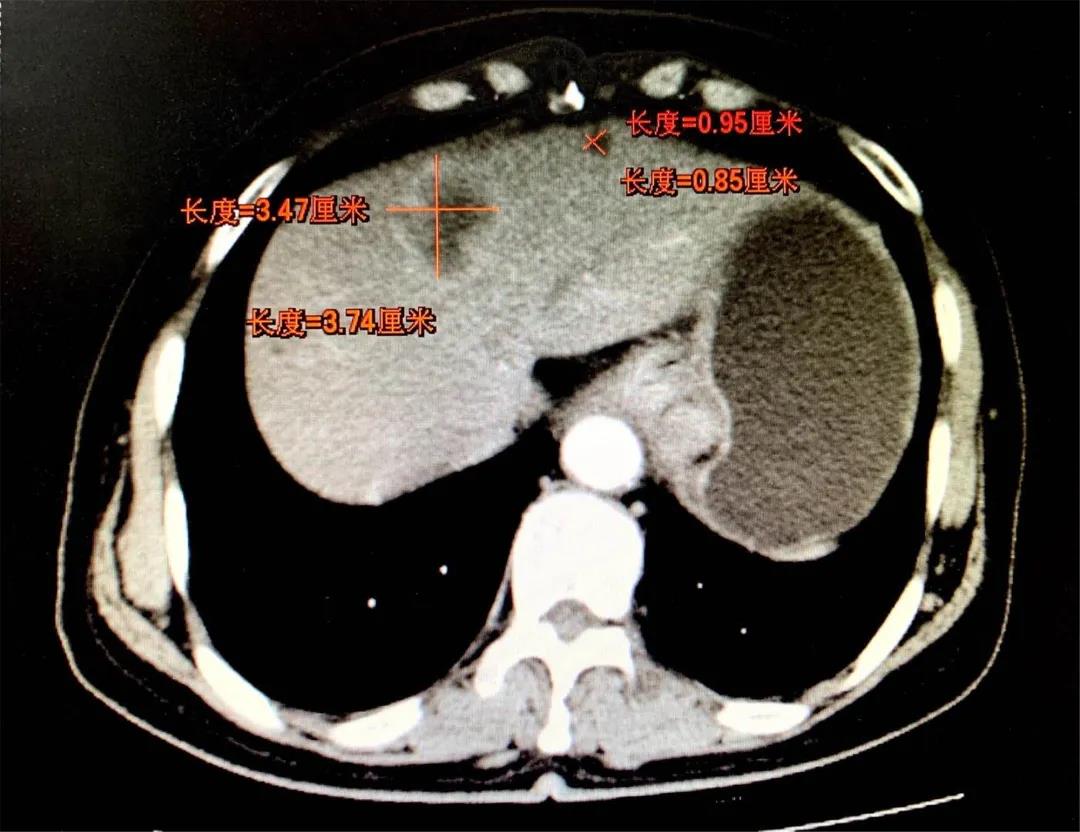

转化2周期

8月前患者就诊于晋城市某医院行胃镜示:胃癌,病理示:腺癌。进一步行腹部增强CT示:贲门胃底小弯侧占位,周围见肿大淋巴结;肝内低密度肿块影,考虑转移。遂就诊于和济医院,入院诊断为:“1.胃癌肝转移(cT4N2M1) 2.肝脏多发囊肿3.原发性高血压(2级,低危组)4.卵巢囊肿切除术后”。经医院消化病中心MDT讨论,并与患者及家属充分沟通后,决定先为其行转化治疗(方案:DOS)。转化治疗2个周期后患者症状明显好转,体重增加约10kg。肿瘤原发病灶较前缩小、肝脏转移灶较前缩小。继续行转化治疗(方案:DOS)3个周期后,患者肿瘤原发病灶较前增大、肝脏转移灶较前继续缩小。经和济医院消化病中心再次MDT讨论并与患者及家属充分沟通后,决定手术治疗。术中胃肠外科张晋杰医师、张康康医师先行腹腔镜辅助根治性全胃切除术+D2淋巴结清扫+Roux-en-Y吻合术,术中邀请肝胆外科主任程丹桂主任医师、刘军廷副主任医师以及超声室武鹏副主任医师行彩超定位下左肝转移病灶射频消融术。术中射频消融在保证对左肝转移病灶精准处理的前提下,对肝脏以最小的创伤,起到最佳的治疗效果,整个手术创伤小,术后第3日开始进流食,5日行上消化道造影提示:未见吻合口瘘。目前患者已恢复正常进食,痊愈出院。